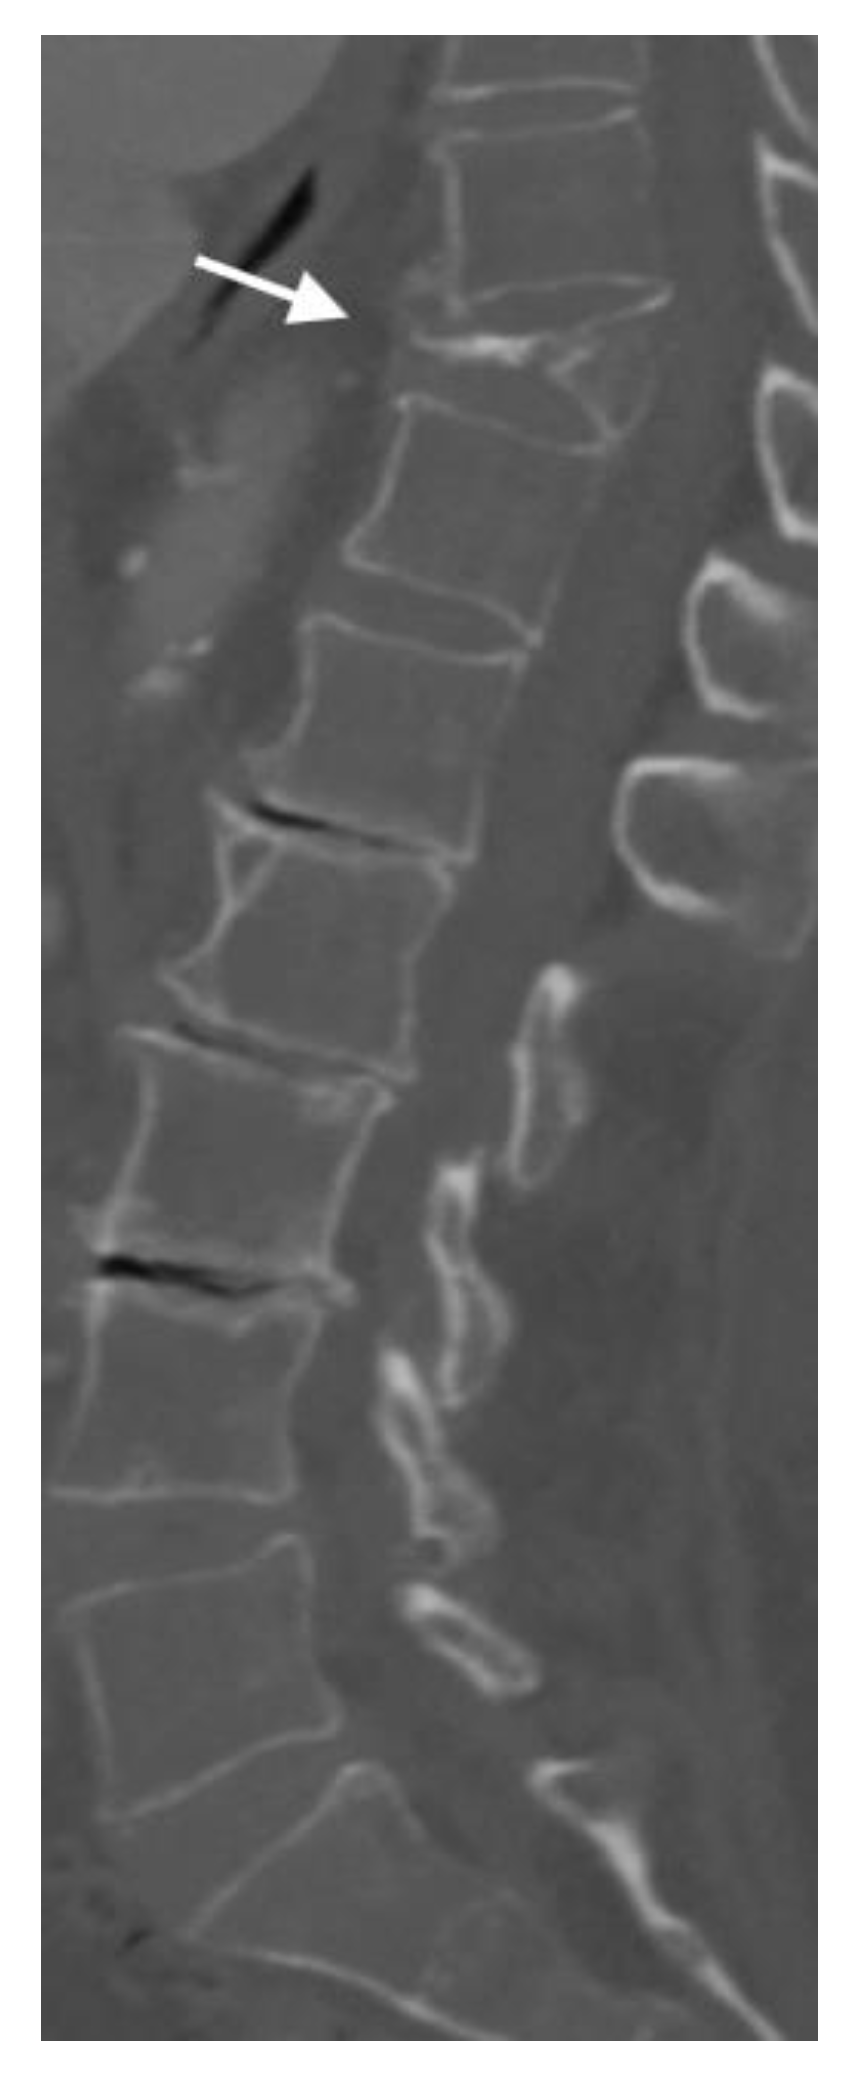

4.2. CT Scans